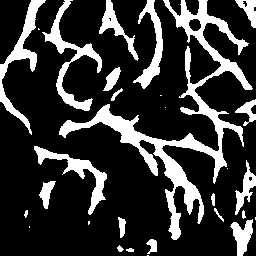

Semantic segmentation of blood vessels is an important task in medical image analysis, but its progress is often hindered by the scarcity of large annotated datasets and the poor generalization of models across different imaging modalities. A key aspect is the tendency of Convolutional Neural Networks (CNNs) to learn texture-based features, which limits their performance when applied to new domains with different visual characteristics. We hypothesize that leveraging geometric priors of vessel shapes, such as their tubular and branching nature, can lead to more robust and data-efficient models. To investigate this, we introduce VessShape, a methodology for generating large-scale 2D synthetic datasets designed to instill a shape bias in segmentation models. VessShape images contain procedurally generated tubular geometries combined with a wide variety of foreground and background textures, encouraging models to learn shape cues rather than textures. We demonstrate that a model pre-trained on VessShape images achieves strong few-shot segmentation performance on two real-world datasets from different domains, requiring only four to ten samples for fine-tuning. Furthermore, the model exhibits notable zero-shot capabilities, effectively segmenting vessels in unseen domains without any target-specific training. Our results indicate that pre-training with a strong shape bias can be an effective strategy to overcome data scarcity and improve model generalization in blood vessel segmentation.